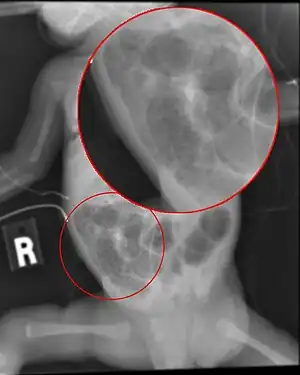

| Radiograph of a baby with necrotizing enterocolitis | |

The diagnosis is usually suspected clinically but often requires the aid of diagnostic imaging modalities, most commonly radiography. Specific radiographic signs of NEC are associated with specific Bell's stages of the disease:[6]

- Specific radiologic signs (pneumatosis intestinalis or portal venous gas

- Severe radiologic signs (pneumoperitoneum)

Ultrasonography has proven to be useful as it may detect signs and complications of NEC before they are evident on radiographs, specifically in cases that involve a paucity of bowel gas, a gasless abdomen, or a sentinel loop.[8] Diagnosis is ultimately made in 5–10% of very low-birth-weight infants (<1,500g).[9]